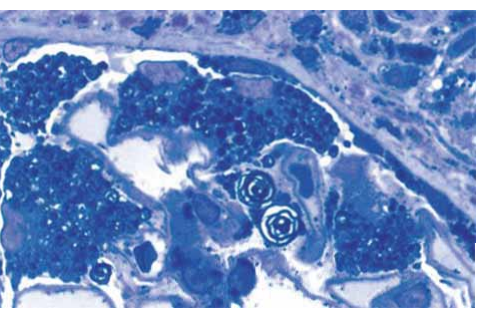

Observe a imagem a seguir.

Coloração azul de Toluidina

(Arquivo pessoal, imagem usada com autorização)

Segundo a imagem histológica, qual o diagnóstico?